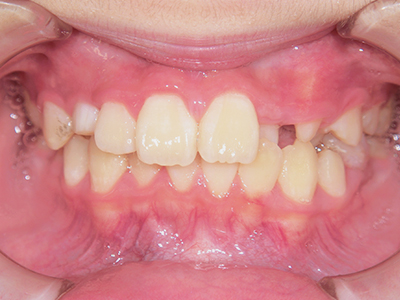

歯並びの相談に来られるお子様は、口呼吸をしているケースが多く、これが歯並びに大きな影響を与えています。

- 口呼吸をしている

↓ - 舌の位置が悪くなる

↓ - 頬の圧力が上の歯列にかかりやすくなる

↓ - 上あごが狭くなる

↓ - 下あごが狭くなる・下あごの位置が悪くなる

↓ - さまざまな不正咬合が生じる